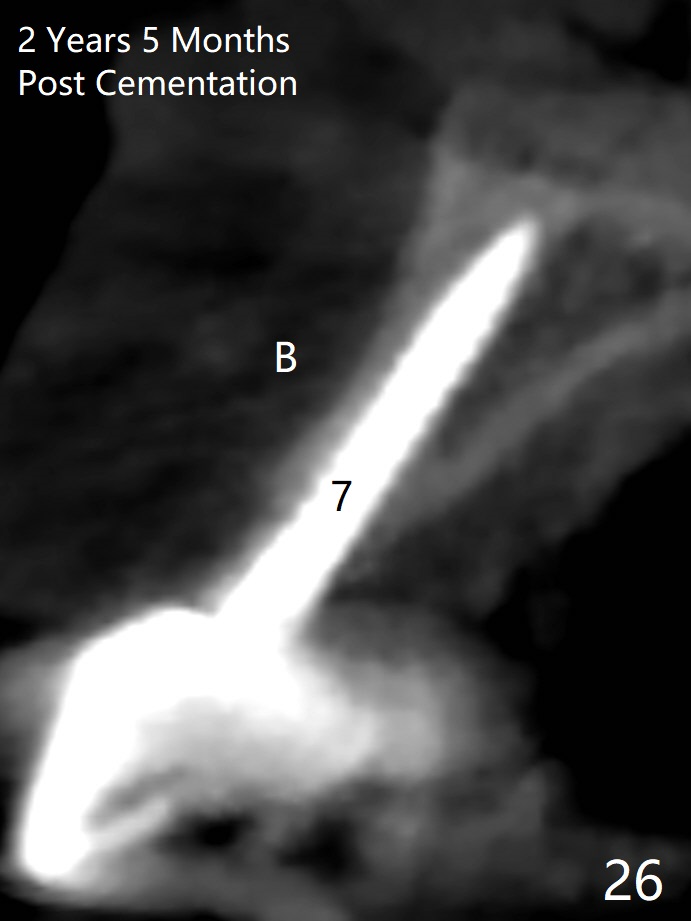

Since the ridge at #7 is ~ 4 mm, a 2.5x14 mm 1-piece implant is placed (Fig.8) after 1.2 mm (Fig.7), and 1.5 mm drills at 12 mm and 2 mm drill at 8 mm. Later the implant is placed deeper (Fig.10). There is no bone loss 7 or 12 months postop, respectively (Fig.11,12). After Diode gingivectomy, there is papillary formation (Fig.13). No provisional is provided after impression (with the abutment torqued at #6) for oral hygiene. With access holes at #6 and 7, crowns are bonded with minimal residual cement (Fig.14 <, which is removed later). There is no hard (Fig.15,16) or soft (Fig.17 *) atrophy 26 months postop, i.e., 13 months post cementation, due to the presence of socket shield (Fig.15 <, as compared to Fig.1). In fact the tooth #8 has mobility and fremitus (short root/poor crown/root ratio, Fig.16); occlusal adjustment is done 13 months post cementation. The crown is dislodged 2 years 1 month post cementation; a prefabricated post is being tried in (Fig.18). There is no atrophy, bone loss or infection at #6 (with socket sheath (*)) or 7 two years 5 months post cementation (Fig.20-27).